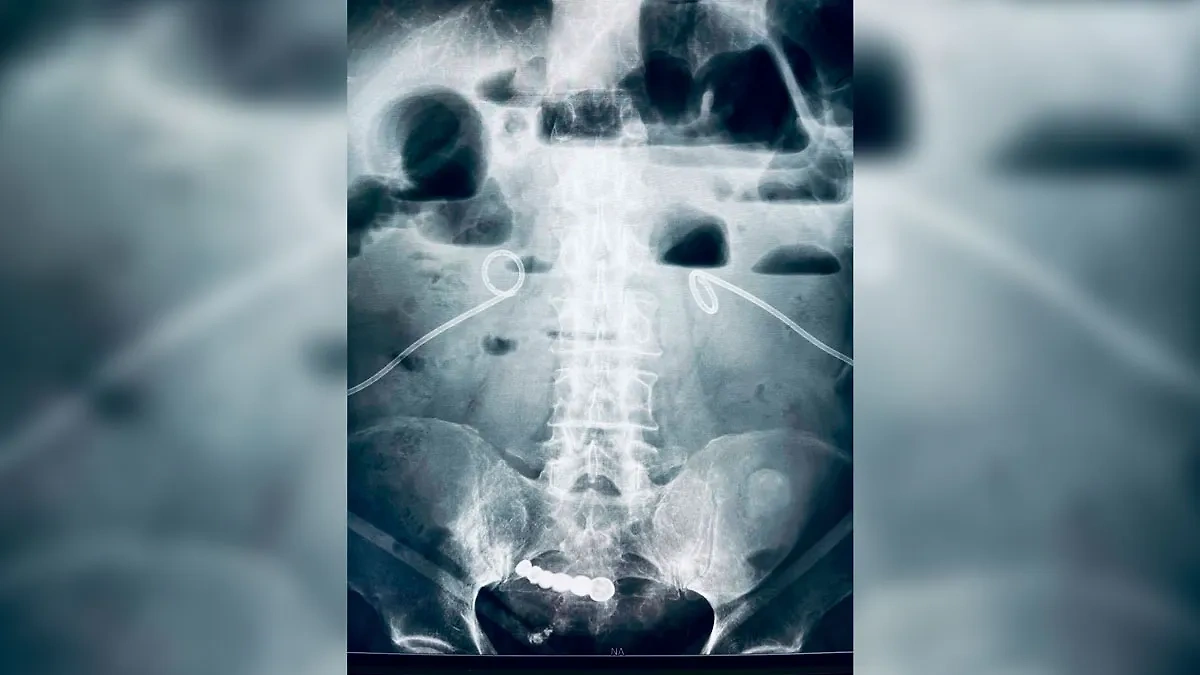

В Кузбассе из живота мужчины извлекли вставную челюсть, проглоченную 6 ...